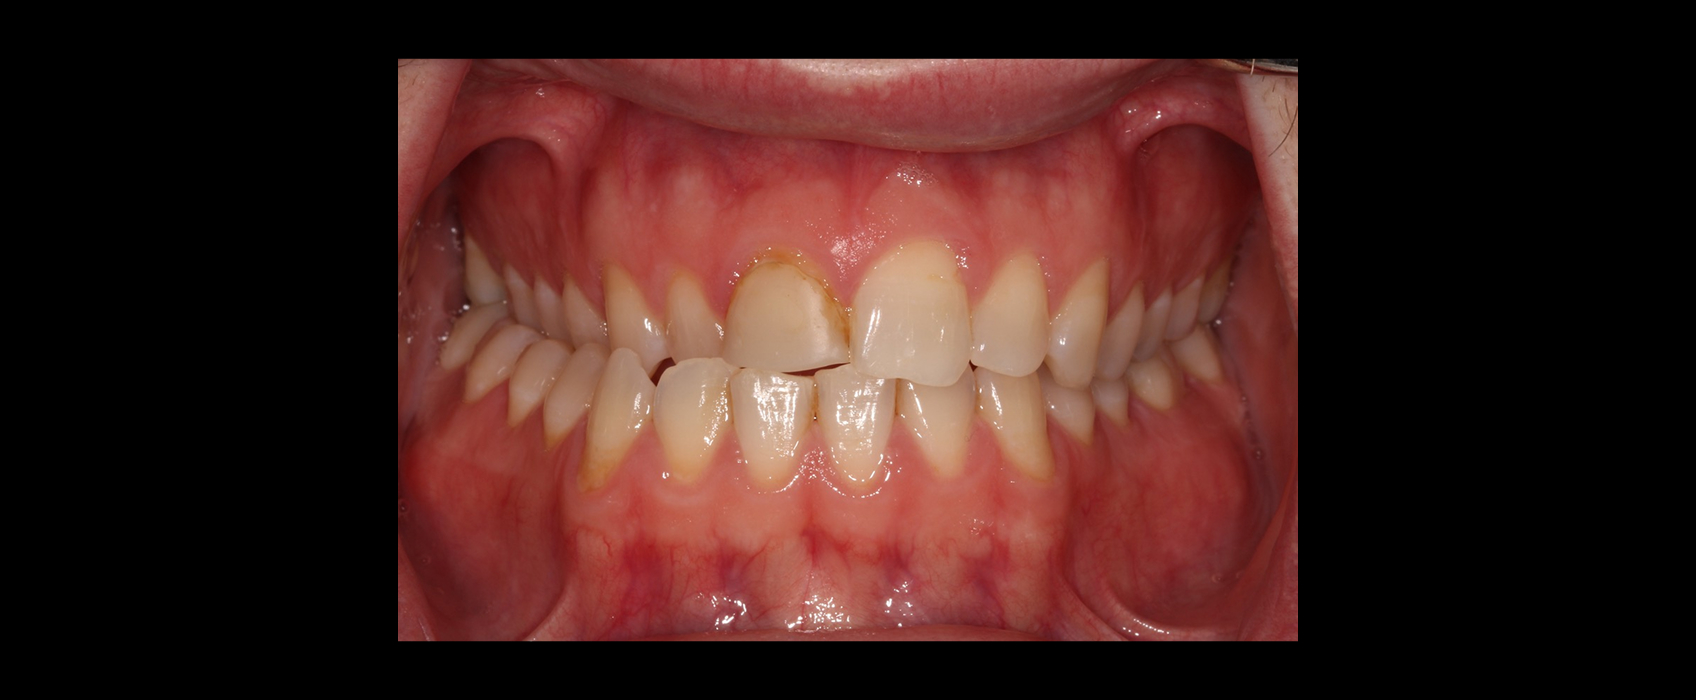

Zach, a patient in his mid-20s, came to our office seeking options for improving his upper front teeth, specifically the noticeable differences in size, shape, and shade between teeth #8 and #9. A childhood bicycle accident had left #8 chipped, and multiple composite restorations over the years hadn’t given him the esthetics he hoped for.

Taking an FGTP approach quickly revealed why restoring #8 had been so challenging. A crossbite was limiting available restorative space, and the gingival position of #8 was more coronal than #9, suggesting supereruption after the original trauma.